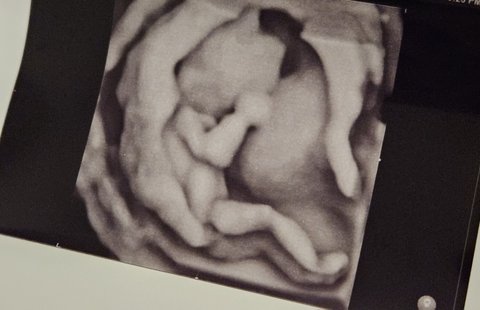

15주 초음파 찍고왔는데

다리가 꽤 긴 것 같기도 하고요

첫째 임신이라 떨리네요.. 건강만 했으면